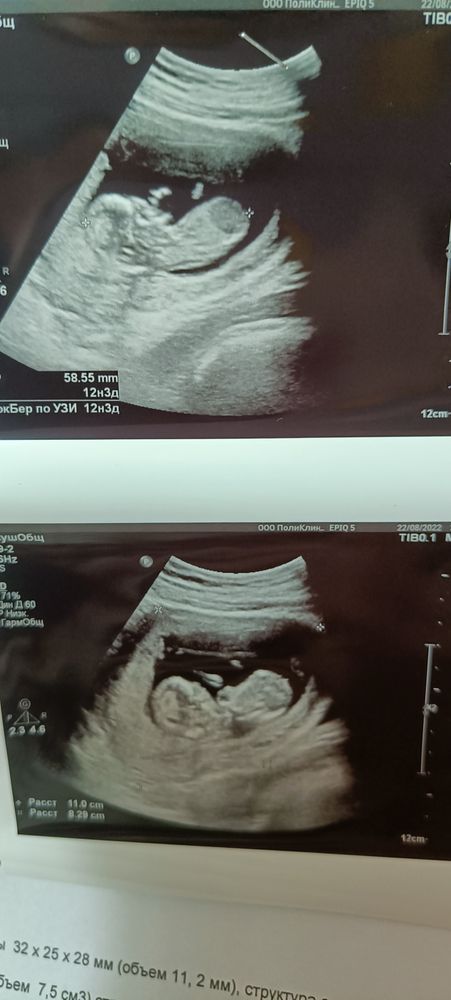

Гадание по УЗИ на пол 😅 12,3 недели

Что видно? Мне ничегошеньки 😅 Толи ракурс такой, толи рано, но я бугорков половых не наблюдаю вобще

Ну я попробую погадать))) у моих мальчиков был более крупный череп, а тут такая аккуратная головочка. Кажется, девочка)

Ракурс не удачный, но малыш прелесть! У нас половой бугорок огромный) , и маленькая надежда на девочку)

Чуток ракурс не дотянут- не видно бугорка🥹придётся подождать до новой встречи! Ну или нипт. Там будет все 100%